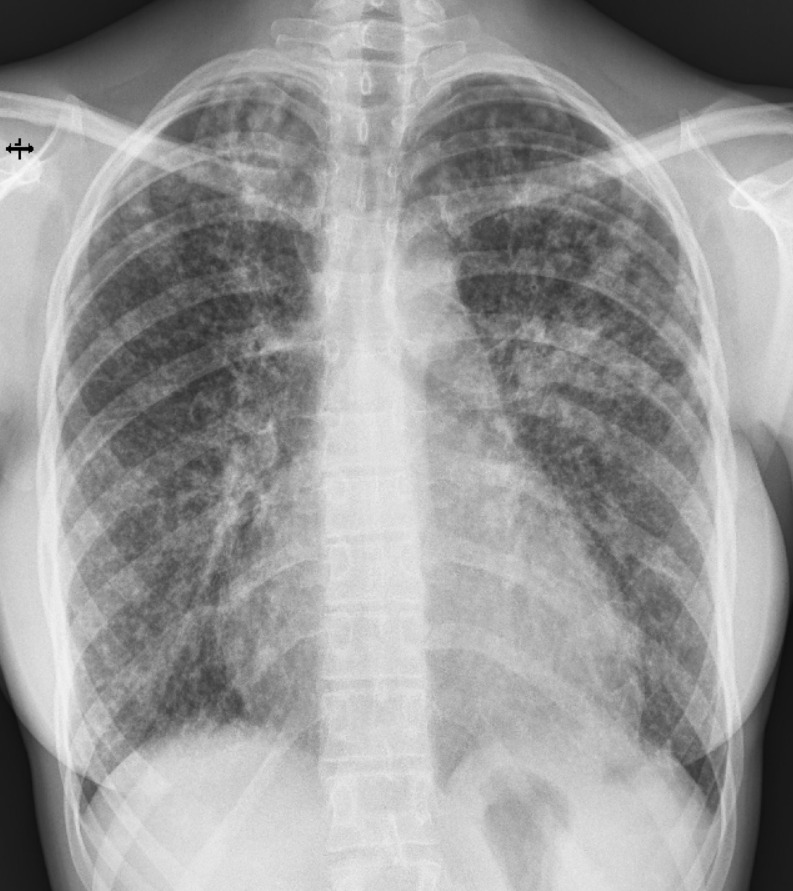

A woman in her 20s presented with a 3-week history of dry cough, exertional dyspnea, and fever, without night sweats or weight loss. She initially consulted her general practitioner, who prescribed antibiotic therapy and referred her for chest radiography. The chest X-ray demonstrated diffuse bilateral nodular opacities, consolidation in the left upper lobe, and cardiomegaly with an estimated cardiothoracic ratio of 0.64 (Figure 1). Based on these findings, she was referred to the Emergency Department of a tertiary care hospital the following day.

Figure 2. Non-contrast chest CT scan, lung window (description above in the text).